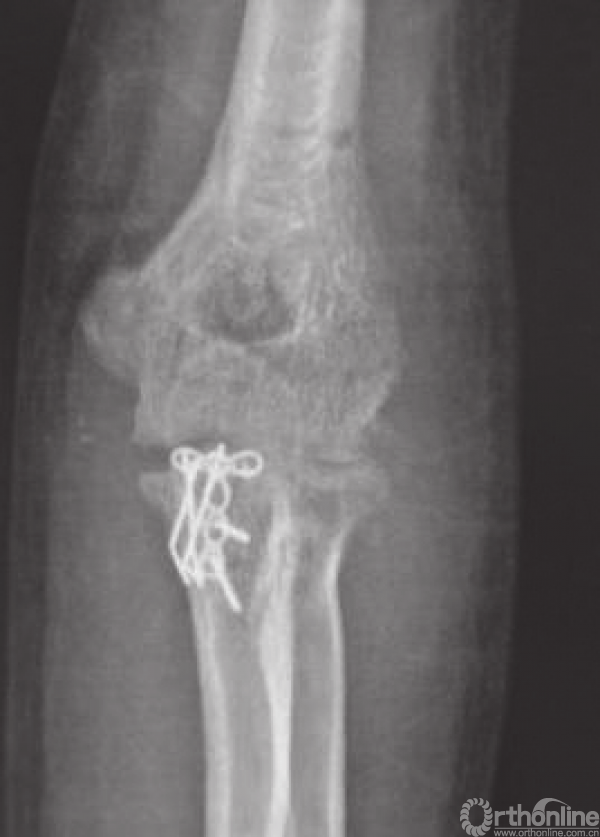

图2患者,男,35岁,左肘关节三联征,冠状突骨折O’Driscoll分型为尖部骨折第二亚型,桡骨头前侧剥脱约10%,Mason分型Ⅱ型

c.术后6个月正位X线片示骨折愈合,有轻度异位骨化;